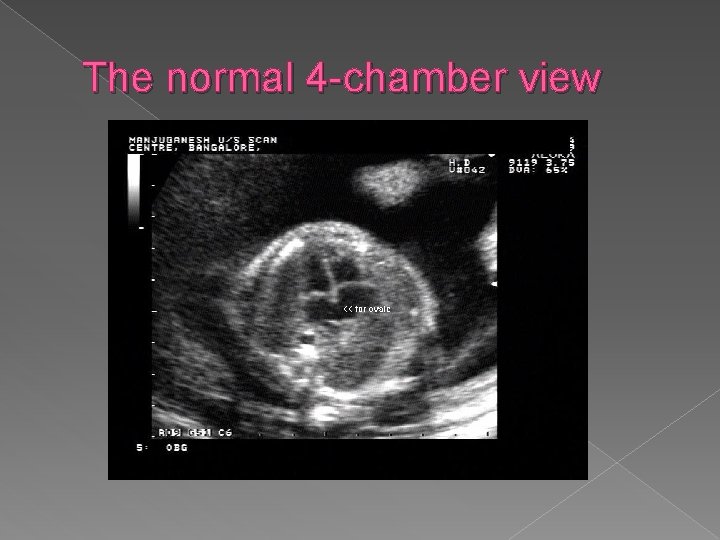

Four chamber view › The 4 cv is the single most important image of the fetal heart. › Normal features are: �Apex of heart points 45 degrees to left anterior chest wall �Ventricles approx. the same size (right can be larger than left in pregnancy) �Flap of foramen of ovale opens into left atrium �Prominent moderator bands present in apex of right ventricle �Valves separate both atria from ventricles

The normal 4 -chamber view

� Normal orientation of the 4 chamber heart view within the fetal chest: the heart should take up 1/3 of the chest cavity with the apex pointing to the left chest wall.